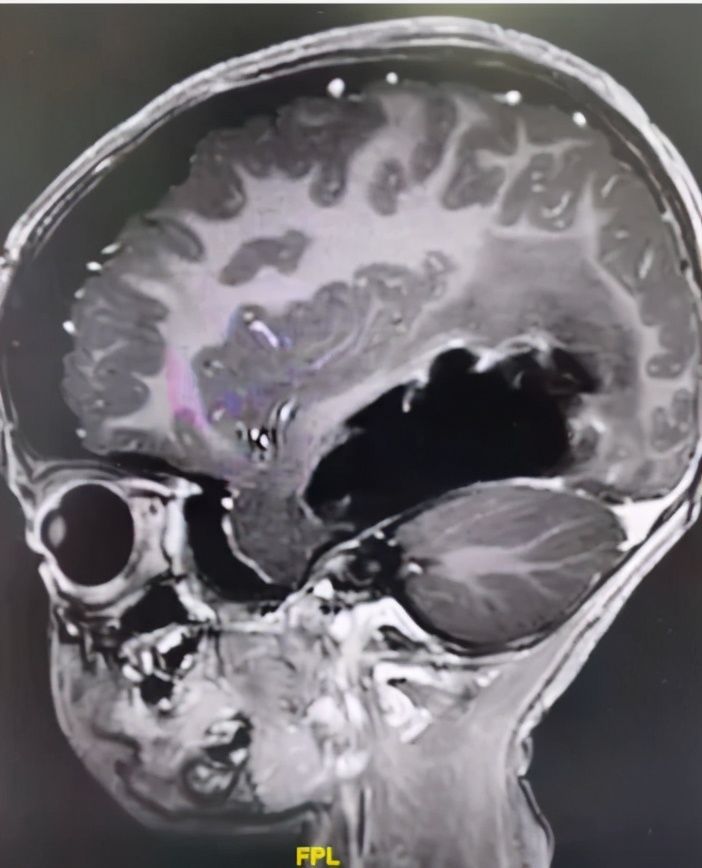

术后MR显示:肿瘤被全切除,脑干也复位了